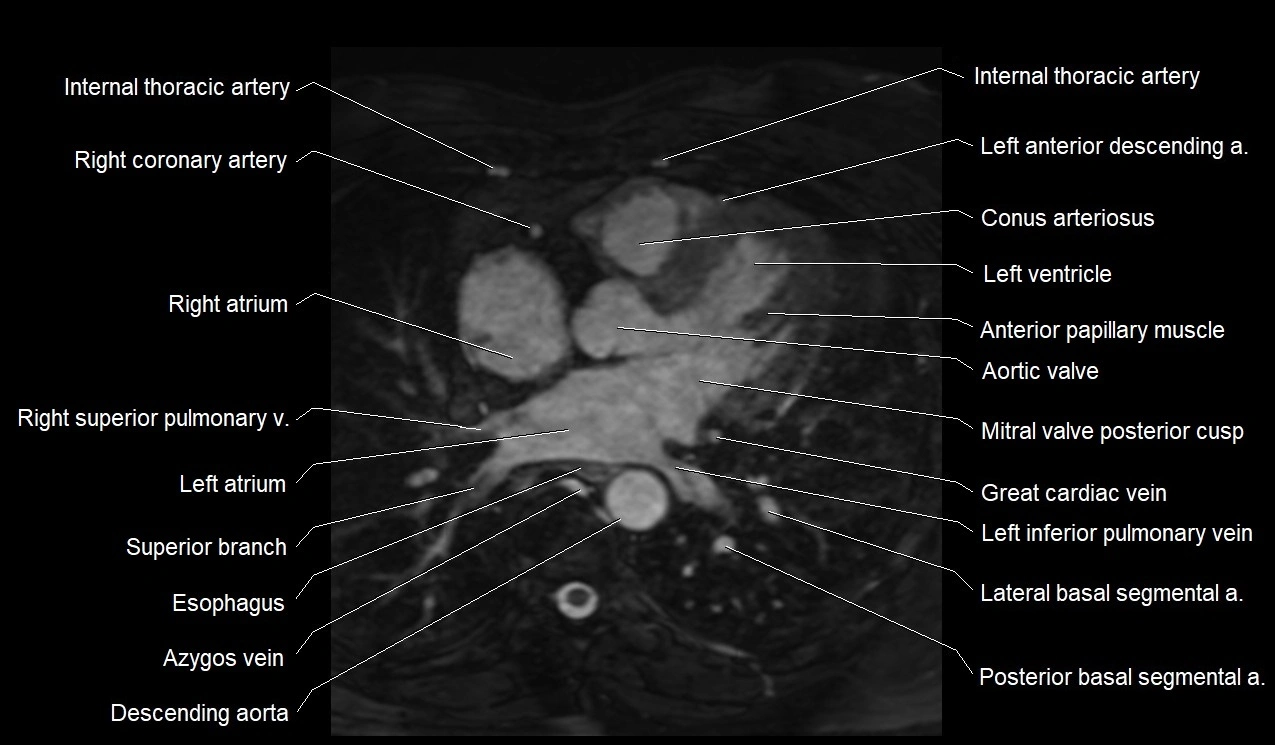

MRI image